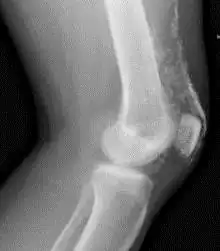

X-Ray of the knee in a person with dermatomyositis.

Magnetic resonance imaging may be useful to guide muscle biopsy and to investigate involvement of internal organs;[21] X-ray may be used to investigate joint involvement and calcifications.[22]